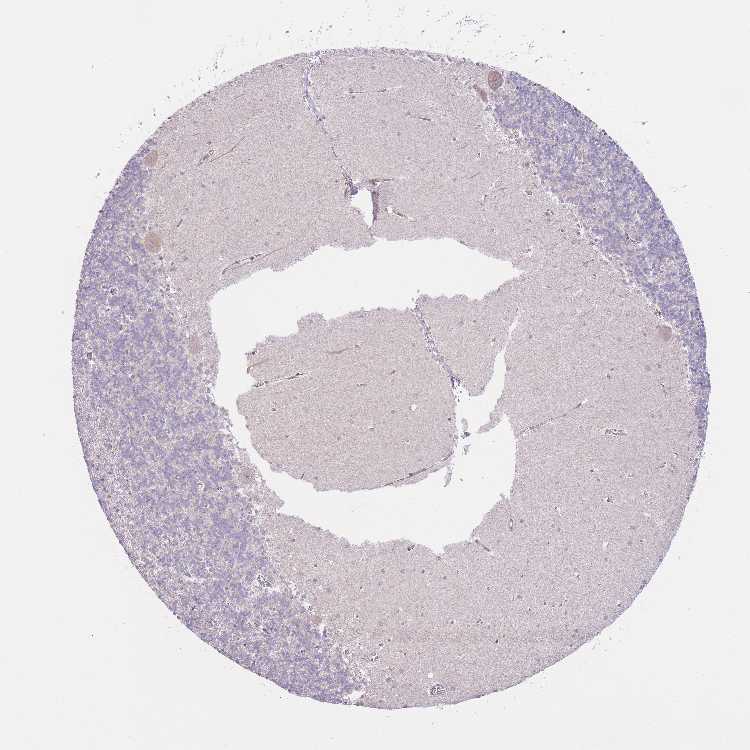

CEREBELLUM - Antibody stainingi

Antibody staining in the annotated cell types in the current human tissue is reported as not detected, low, medium, or high, based on conventional immunohistochemistry profiling in selected tissues. This score is based on the combination of the staining intensity and fraction of stained cells.

Each image is clickable and will lead to virtual microscopy that enables deeper exploration of all samples and also displays staining intensity scores, fraction scores and subcellular localization as well as patient and tissue information for each sample.

Antibody HPA049314Antibody HPA076949

Purkinje cells LowNot detected

Cells in granular layer Not detectedNot detected

Cells in molecular layer Not detectedNot detected